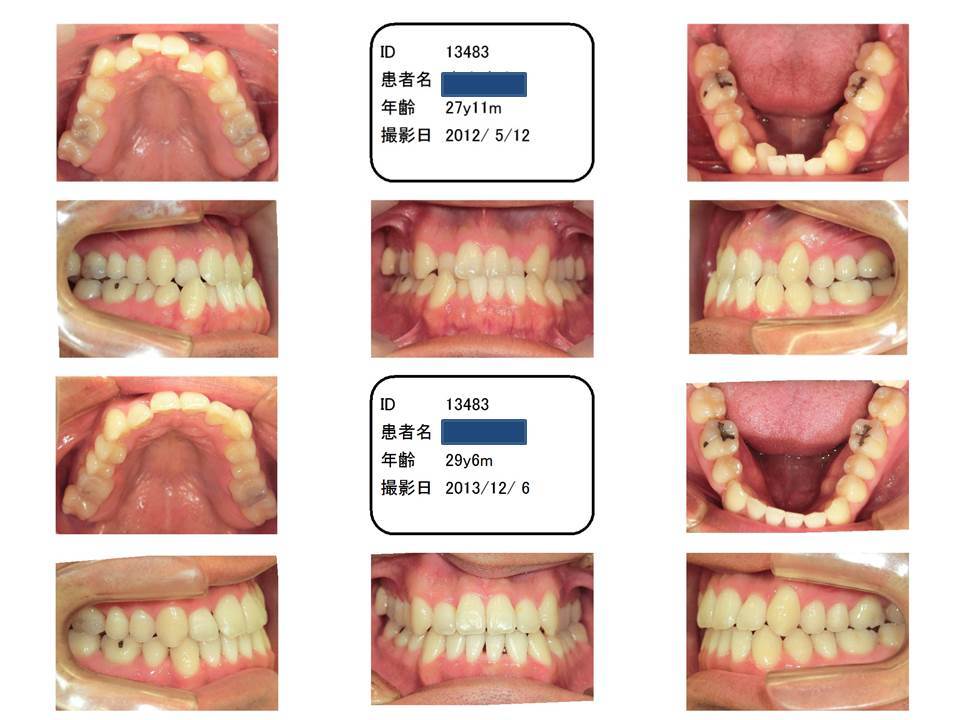

27歳男性 受け口治したいけど、手術はしたくない

手術でしか治療できない症例はもちろん有りますが、当院ではできれば手術なしで治療できないかと模索しています。この症例は、他院では絶対手術なしでは治せないと言われて、当院にお越しになられました。

当院ではこのくらいの反対咬合であれば、手術なしで矯正治療します。もちろん、手術という選択肢を取ることもできます。

手術を併用すると、下顎自体を下げることができるので、横顔をもっと変化させることができます。

前から見た笑った感じは、どちらにしてもかなりイメージが変わります。手術をした方が、より学術的な理想に近づきますが、手術を併用しないと大変なことになるとかはありません。手術なしでも、絶対に矯正治療した方が圧倒的によい状態になることは間違いありません。

右下一本歯を抜いて、ブラケット装置にて治療。